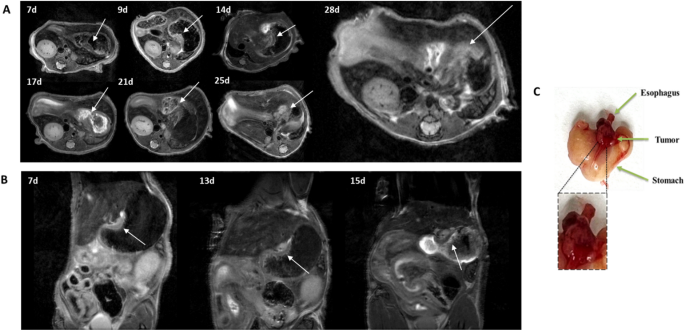

Xenograft tumors of non-treated animals (n = 3) were also cryopreserved and successfully implanted as orthotopic tumors into the esophagus of recipient mice. Tumor growth was monitored via bi-weekly MRI starting 7 days post-surgery. As it is possible to observe from the T2w images of the orthotopic model in Fig. 1, tumor appears to grow along the site of induction, with a tendency to infiltrate into the esophagus and stomach. Macroscopically, when it grows on site, it appears as a globe-like structure clearly defined and identifiable (Fig. 1C). Infiltration seem to properly mimic the clinical development of this type of tumors.

Representative T2-weighted images of (A) animal R02 (axial) and (B) animal R06 (sagittal) showing tumor growth at different time points (arrow indicates the tumor). (C) Representative image of stomach, tumor and esophagus as seen during necroscopy.

The morphological analysis of excised specimens highlighted the presence of a tumor mass and residual surrounding tissues, esophagus and stomach, confirming that the lesion was developed in correspondence to the induction site. Tumors from OE-19 cells displayed the characteristics of an esophageal adenocarcinoma, in which epithelial tumor cells were organized in a fibrovascular stroma (Fig. S1A). Immunofluorescence staining of an adjacent tissue section showed that HER-2 expression was restricted to epithelial tumor cells with no expression in the surrounding tissues (i.e., tumor stroma, esophagus and stomach) (Fig. S1B).